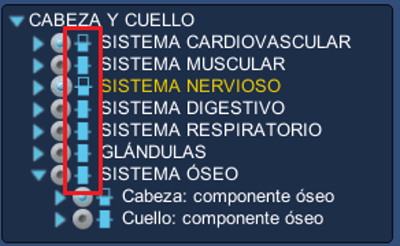

3. En

el explorador de órganos seleccione

los órganos o sistemas que desea cortar, haciendo clic en la barra rectangular que se encuentra

al lado izquierdo del nombre del órgano.

La barra se ve en dos colores, indicando cuales órganos o sistemas han sido cortados.